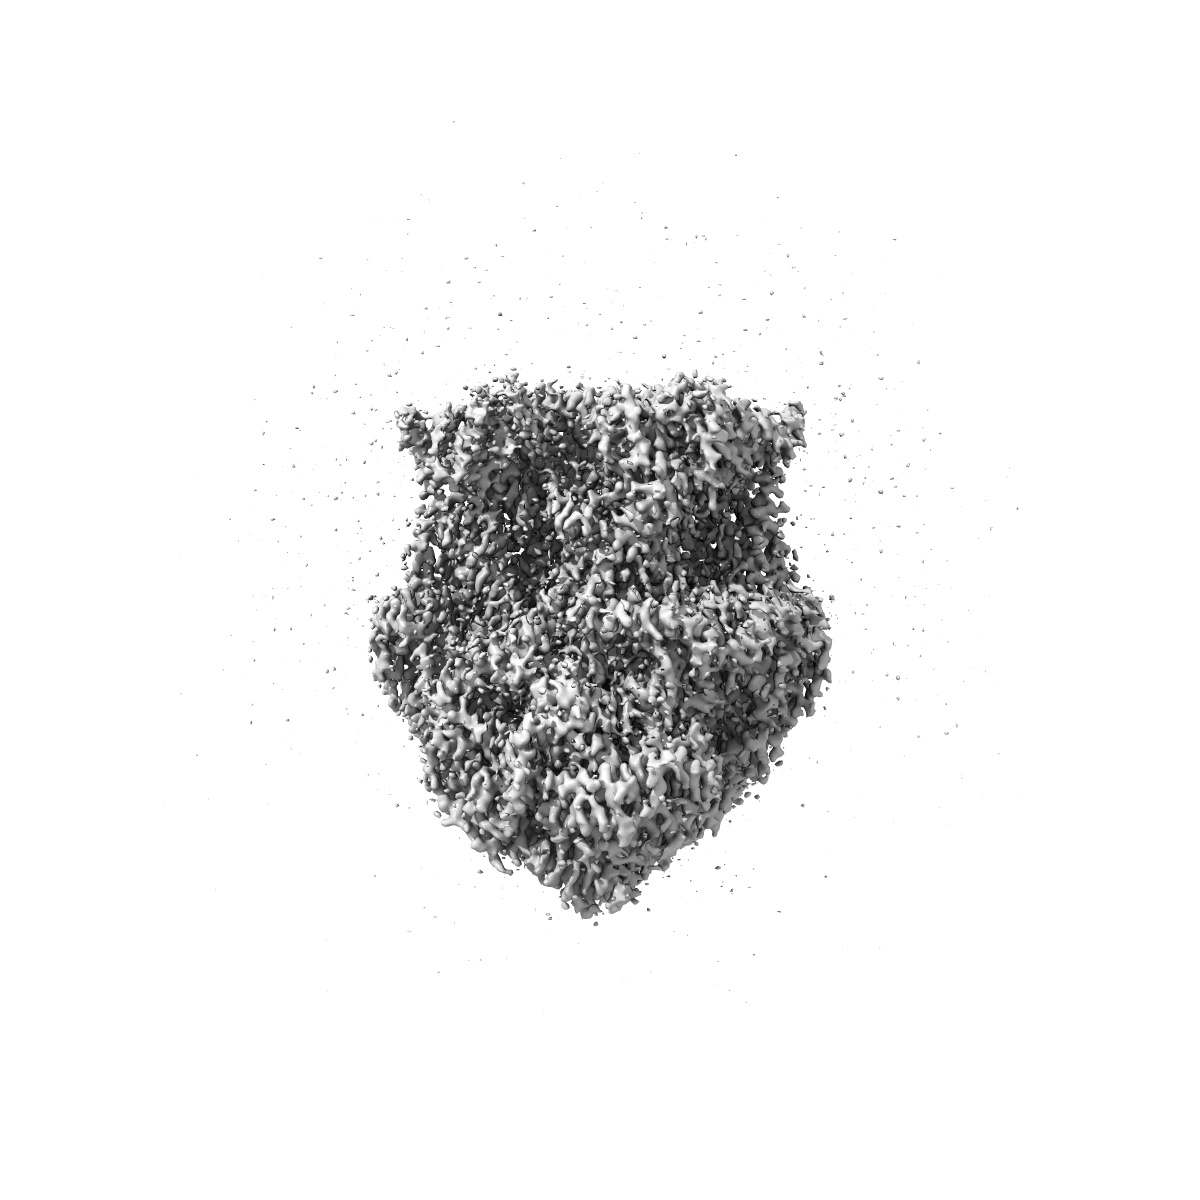

Toxoplasma gondii cytochrome bc1 complex from the respiratory supercomplex III2-IV inhibited by atovaquone and ELQ-300

Sample: cytochrome bc1 complex (III2)from the respiratory chain supercomplex III2-IV from Toxoplasma gondii

Fitted models: 9i4x

Structure, assembly and inhibition of the Toxoplasma gondii respiratory chain supercomplex.

PUBMED: 40389671

DOI: doi:10.1038/s41594-025-01531-7